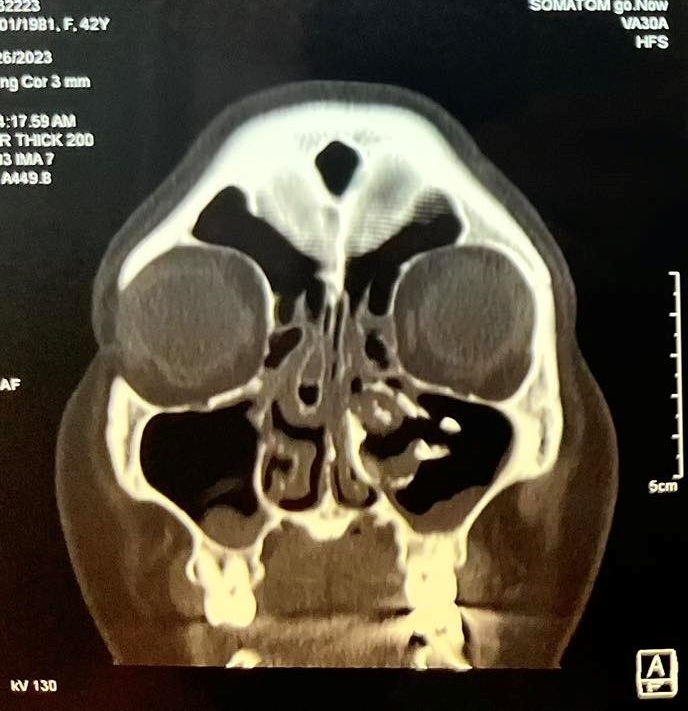

Bệnh nhân nữ, 42 tuổi, không có tiền căn chấn thương vùng hàm mặt trước đó, là công nhân của công ty may mặc, bệnh nhân luôn có cảm giác nghẹt mũi trái, cảm giác dịch nhầy chảy từ mũi xuống họng nhưng không khạc ra được, các cảm giác nhức vùng mặt cùng bên ngày càng rõ nên bệnh nhân đã đi khám nhiều nơi điều trị nhưng bệnh vẫn không thuyên giảmGần đây bệnh nhân xuất hiện thêm đau nhức vùng mắt trái cùng bên nên đã đến khám tại Bệnh viện Quận 4. Qua nội soi thăm khám và thực hiện chụp CT-Scan phát hiện bệnh nhân có cấu trúc mật độ giống xương dính vào thành trong xoang hàm bên trái, đẩy lệch vách mũi xoang về phía vách ngăn gây hẹp hốc mũi bên trái kèm viêm xoang hàm sàng 2 bên và concha bullosa cuốn mũi giữa bên phải gây tắc nghẽn đường dẫn lưu của xoang hàm bên phải

Hình ảnh CT scans mũi xoang